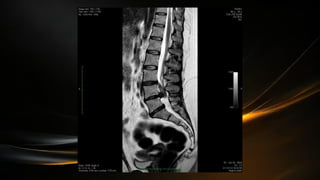

• Se extiende desde la articulación atlantooccipital hasta el borde

superior de la segunda vertebra lumbar (L2)

• En el extremo caudal la medula espinal termina en forma de cono

(cono medular) de esta porción sale el filum terminale que desciende

hasta el cóccix